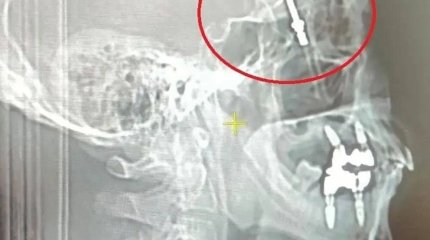

"Сын не может есть и пить": жительница Алматы обратилась в полицию с жалобой на детских стоматологов